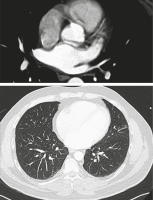

Computertomographie

Abbildung 3: Computertomographie April 2021

Keywords:

,

Pneumologie

Pulmonalvenenstenose

PVS